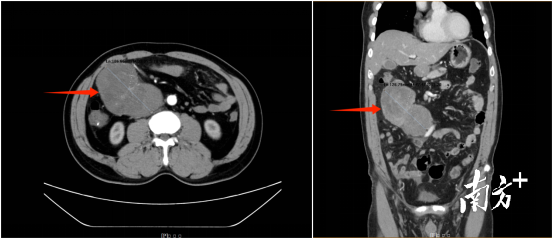

李叔来到南医三院普通外科求医。入院后医生们对李叔进行了详细的体查,发现腹腔肿物占位明显,站立时腹部明显隆起,而且肿物可在右腹部体表触及,质地较韧,无压痛,可推动,与周围无明显粘连。为进一步评估腹腔肿物的情况,李叔进行了全腹CT+增强检查,结果发现右侧中腹部大小约为166毫米×100毫米×92毫米肿物,与附近重要组织、器官及血管位置紧密相邻并且将其往周围推移。由于李叔并无明显腹部及全身不适症状,导致肿物隐匿性生长至如此巨大。